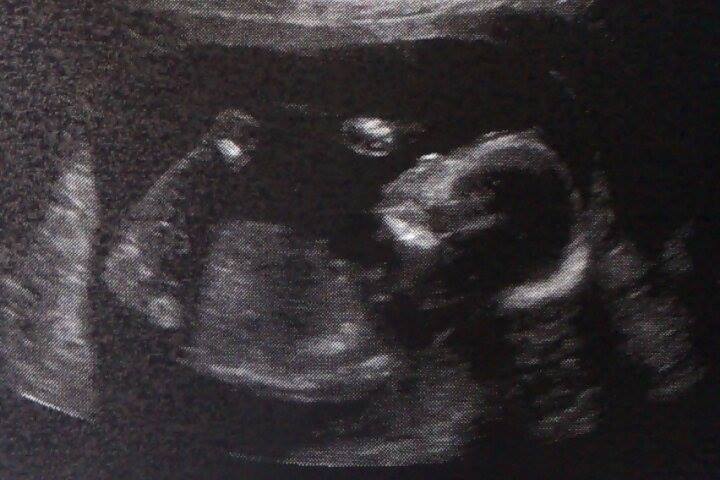

Attachment 18067 @ 18 weeks :)

I don't think the nub theory works this late. I don't see any gender clues.

No gender clues

Do you have any potty shot pictures? x